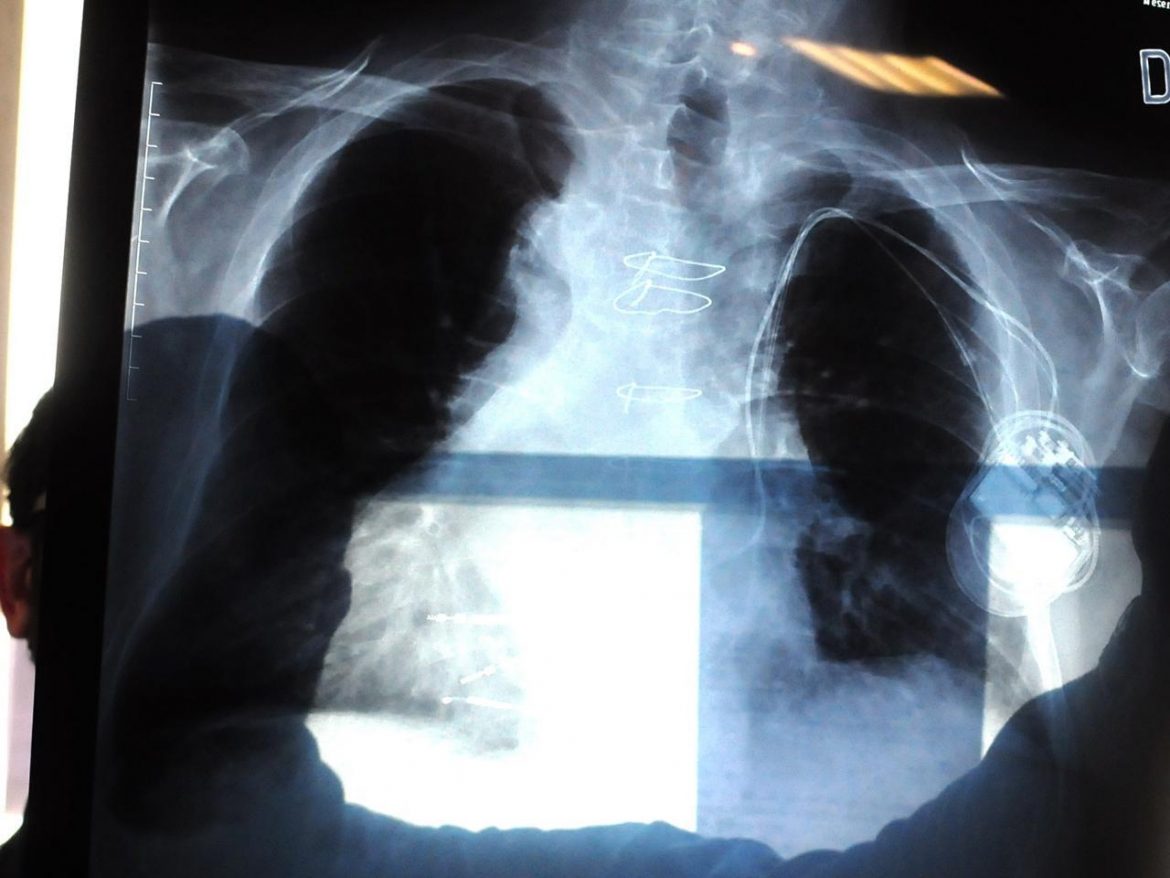

Milano, 13 gen. (Adnkronos Salute)() – La Commissione europea ha concesso l’Autorizzazione all’immissione in commercio condizionata per sotorasib (Lumykras*), inibitore di KRASG12C first-in-class, nel trattamento di pazienti adulti affetti da cancro del polmone non a piccole cellule (Nsclc) in stadio avanzato con mutazione KRASG12C e in progressione dopo almeno una precedente linea di terapia sistemica. L’autorizzazione completa per questa indicazione è subordinata alla verifica e alla descrizione del beneficio clinico in uno o più studi confirmatori, precisa l’azienda americana Amgen.Il cancro del polmone non a piccole cellule – ricorda la compagnia in una nota – rappresenta circa l’84% dei 2,2 milioni di nuove diagnosi di carcinoma polmonare individuate ogni anno a livello globale, inclusi i circa 400mila nuovi casi in Europa. In Italia il tumore al polmone è la seconda neoplasia più frequente negli uomini (14%) e la terza nelle donne (7%), con circa 41mila nuovi casi stimati nel 2020. La mutazione KRASG12C è una delle più frequenti nel Nsclc ed è presente in circa il 13-15% dei pazienti europei colpiti da Nsclc non squamoso. Con il via libera Ue, e in funzione delle procedure di rimborso locali, i medici di tutti i Paesi membri dell’Unione, oltre a Norvegia, Islanda e Liechtenstein, potranno mettere a disposizione il farmaco ai pazienti ritenuti idonei.”L’approvazione di sotorasib, prima e unica terapia mirata per Nsclc con mutazione KRASG12C di provata efficacia, potrà garantire un migliore trattamento di tutti i pazienti europei affetti da questa forma di tumore notoriamente difficile da curare – dichiara David M. Reese, vicepresidente esecutivo Ricerca e Sviluppo di Amgen – La storica scoperta scientifica di Amgen ha permesso ai ricercatori di far avanzare nella pratica clinica il primo inibitore di KRASG12C, un’innovazione cruciale che desideriamo rendere disponibile al maggior numero di pazienti in tutto il mondo”.La decisione Ue – dettaglia la nota – fa seguito al parere positivo del Comitato per i medicinali per uso umano (Chmp) dell’Agenzie europea del farmaco Ema e si basa sui risultati dello studio di fase 2 CodeBreaK 100 nel Nsclc. Si tratta della più ampia sperimentazione clinica condotta finora su pazienti con mutazione KRASG12C. Sotorasib 960 mg, in monosomministrazione giornaliera per via orale, ha dimostrato un tasso di risposta obiettiva del 37,1%e una durata mediana della risposta di 11,1 mesi. Le reazioni avverse più comuni sono state diarrea (34%), nausea (25%) e stanchezza (21%). Quelle gravi (di grado ≥3) più comuni sono state: aumento del livello di alanina aminotransferasi (Alt, 5%), aumento di aspartato aminotransferasi (Ast, 4%) e diarrea (4%).